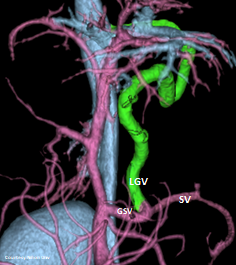

Does LEFT GASTRIC VEIN (LGV) enter the GASTROSPLENIC VEIN (GSV)?

WEISSE 2022

slide10